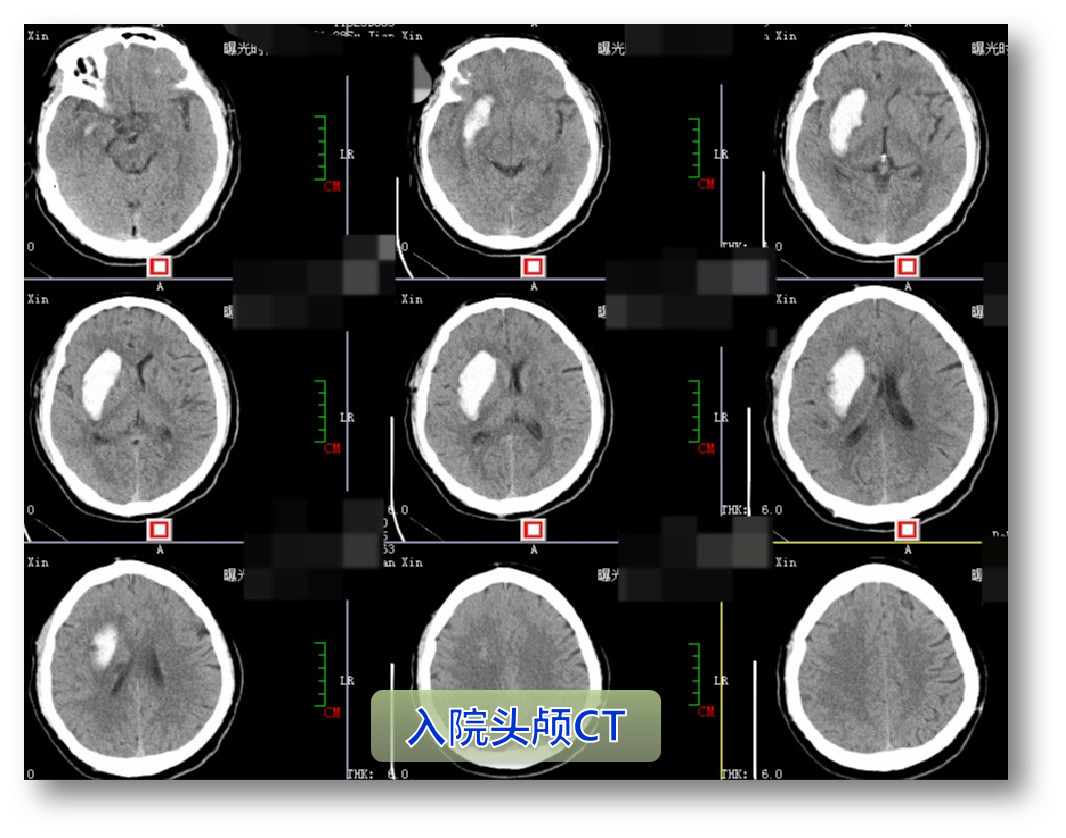

入院时情况

CTA